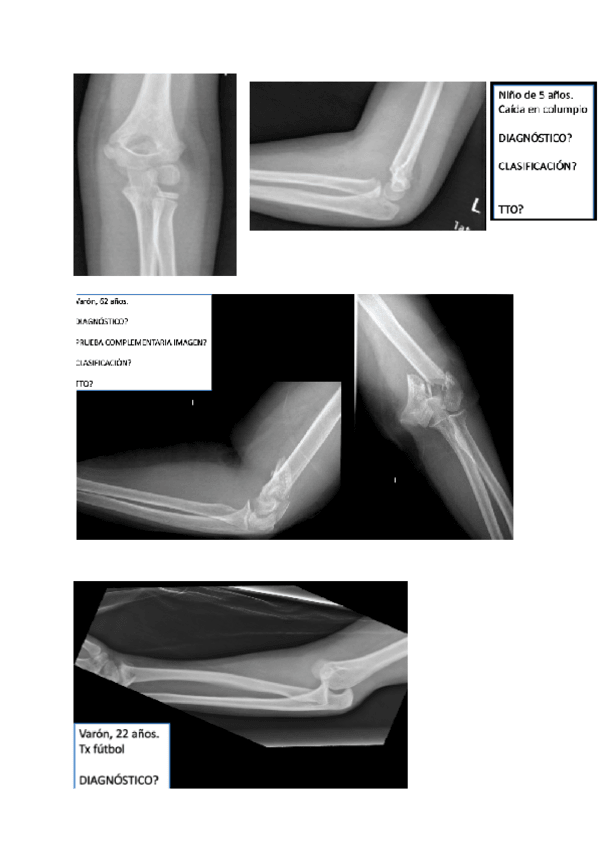

RADIOGRAFIAS PAT.QUIRURGICA

He publicado nuevos apuntes de 2º Patología Quirúrgica: RADIOGRAFIAS PAT.QUIRURGICA

rx-2.pdf

rx-1.pdf